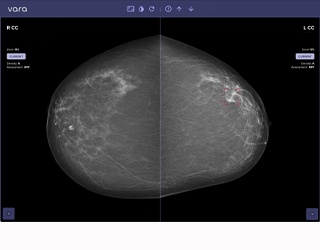

Pünktlich zum Brustkrebsmonat Oktober: Radiologische Allianz setzt künstliche Intelligenz bei der Erkennung von Brustkrebs ein